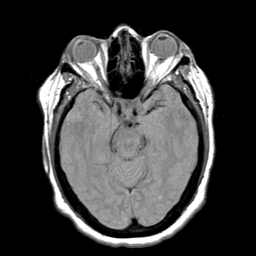

Cerebral hemorrhage, MR Study mr-pd -- Slice #9

[Home][Help][Clinical] Slice 9